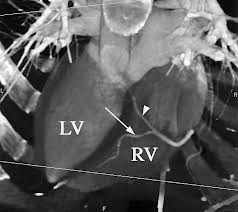

Resonancia magnetica cardiovascular corazón. La resonancia magnética cardiaca (RMC) es un una técnica de imagen para el estudio no invasivo del corazón, inocua ya que no utiliza radiación, bien tolerada y segura. Actualmente se encuentra disponible en la mayoría de hospitales. Permite estudiar en una sola exploración la función y estructura del corazón. Ofrece una imagen detallada del corazón, incluidas las cavidades y las válvulas. Está indicada para el estudio anatómico y funcional de cardiopatías congénitas, el origen anómalo de las coronarias, estudio de viabilidad y de perfusión del músculo cardiaco (con administración de contraste), estudios de función ventricular, estudio de miocardiopatías (enfermedades del músculo cardiaco), enfermedades del pericardio (capa de tejido que recubre al corazón) y masas cardiacas.

Una resonancia magnética proporciona imágenes detalladas del corazón y los vasos sanguíneos desde múltiples planos. Con frecuencia, se emplea cuando se necesita más información después de que a usted le han hecho una ecocardiograma o una tomografía computarizada del corazón.